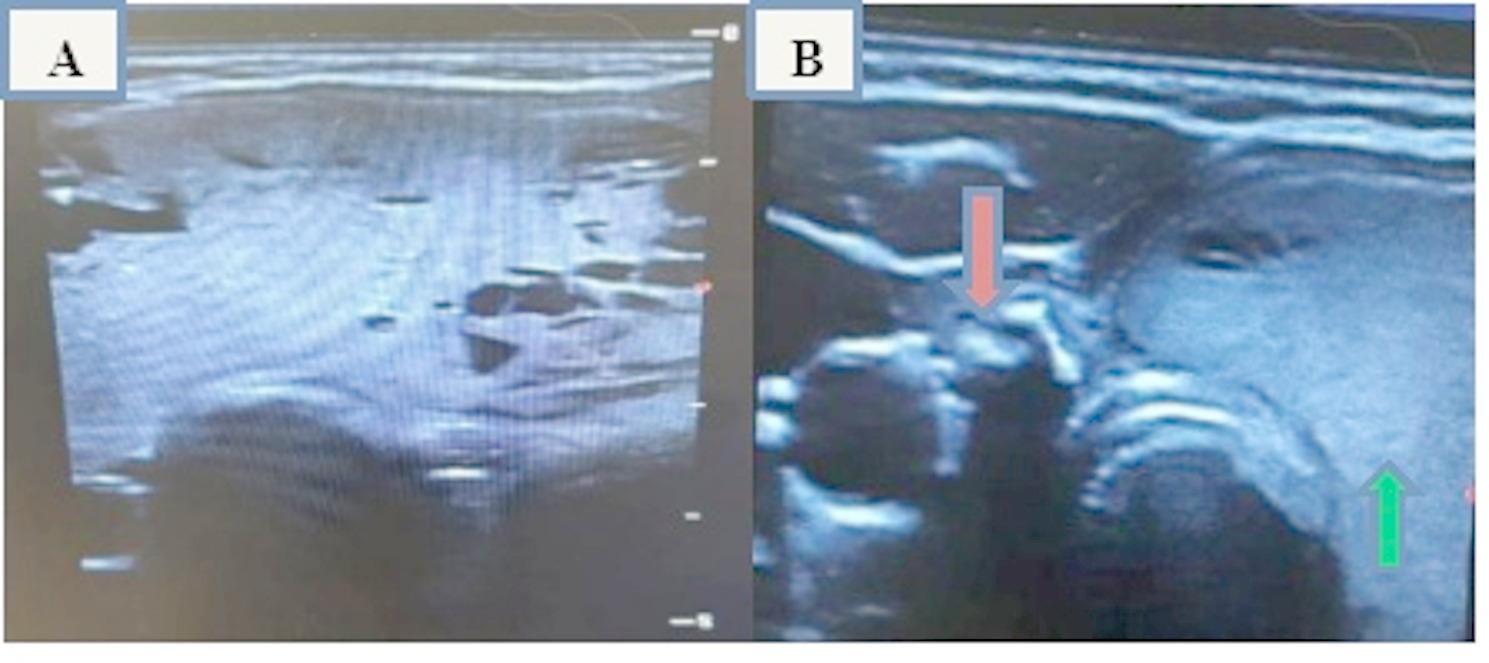

Thyroid hemiagenesis (THA) is a rare congenital disorder in which one thyroid lobe fails to develop. A variety of pathological conditions can occur in the remaining thyroid tissue in association with this rare anomaly such as subacute thyroiditis, colloid nodules, Graves' disease, simple goiter, Hashimoto thyroiditis, adenoma and thyroid carcinoma. The association of thyroid hemiagenesis with simple diffuse goiter is rare, and very few cases have been reported in the literature. A 30-year-old female patient presented at the thyroid clinic because of anterior neck swelling for approximately 2 years, thus raising the suspicion of a thyroid disorder. Physical examination revealed an approximately 5 × 5 cm anterior neck mass consistent with a goiter. The thyroid function test results were within normal limits. Ultrasonography of the anterior neck (thyroid gland) revealed thyroid hemiagenesis of the right lobe and a contralateral (left) diffusely enlarged thyroid gland, which had areas of tiny cystic components with a spongy appearance. Fine needle aspiration cytology demonstrated that the lesion was a colloid goiter and the patient was on regular follow up with thyroid function tests and ultrasound as the patient was without symptoms. Finally, the diagnosis of right thyroid hemiagenesis with a contralateral simple diffuse goiter was made which was a very rare association. Right sided thyroid hemiagenesis was also a very rare finding compared to left sided.